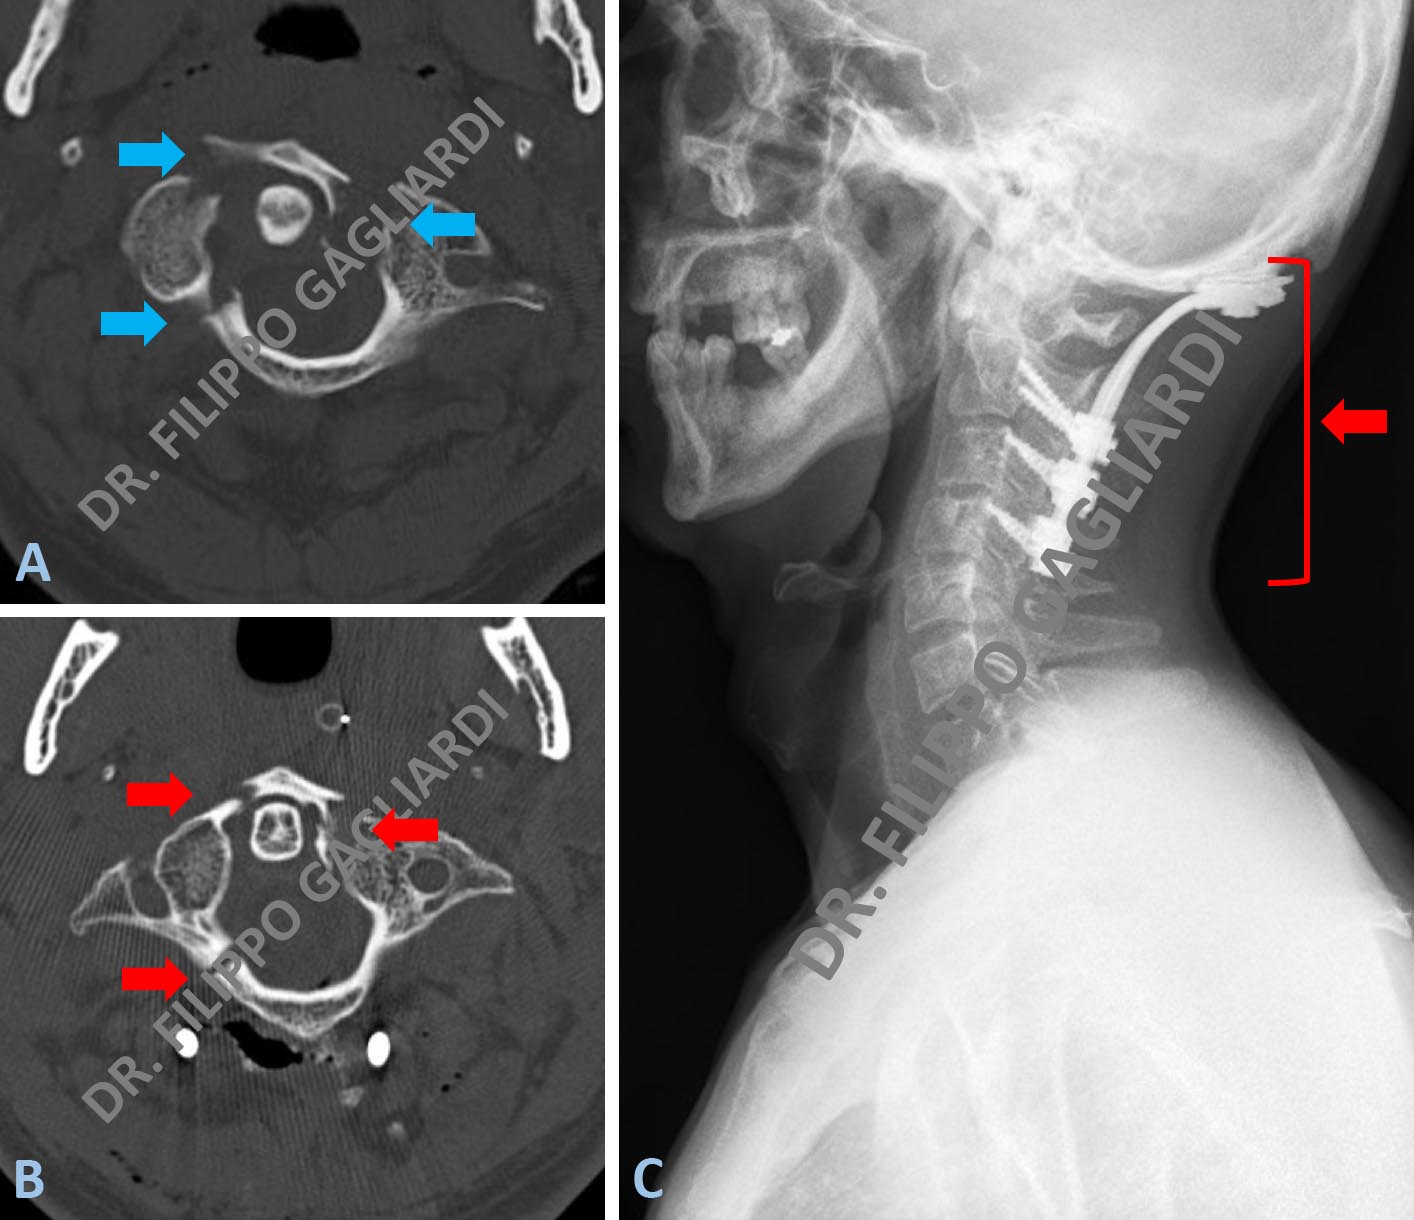

Stabilizzazione cervicale Caso di frattura pluri-frammentaria della prima vertebra cervicale (atlante) (frecce azzurre Figura A). La frattura è stata efficacemente ridotta in sala operatoria (frecce rosse Figura B) e stabilizzata con una intervento di fusione occipito-cervicale con un sistema di viti e barre posizionate a livello della seconda, terza e quarta vertebra cervicale e dell’osso occipitale (freccia rossa Figura C). La Figura A mostra la vertebra fratturata prima dell’intervento, le frecce azzurre mostrano le linee di frattura e il conseguente dislocamento dell’osso. Nella Figura B si vede la vertebra dopo l’intervento con la ricomposizione di tutti i frammenti fratturati. La Figura C mostra i controllo RX post-operatorio con l’impianto in sede.